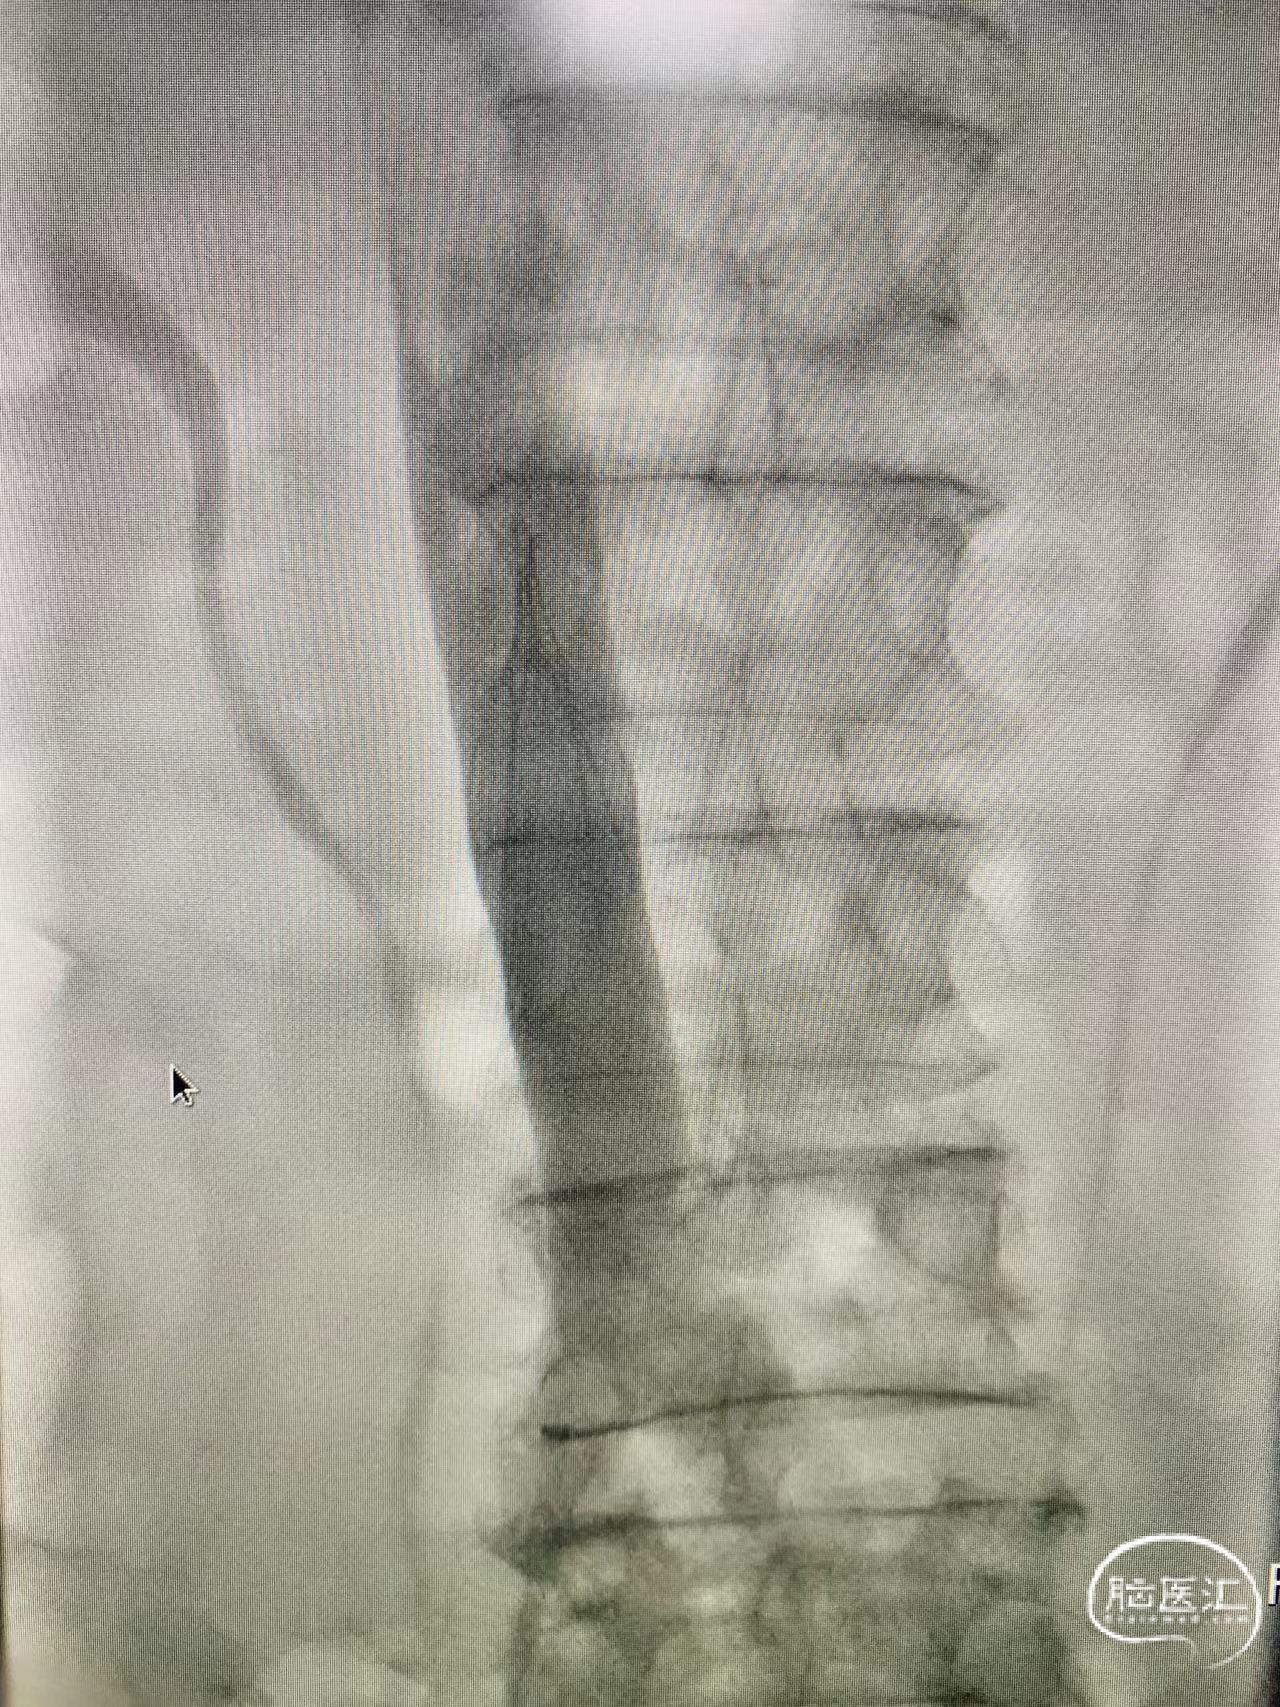

下腔静脉滤器植入手术

成功完成,滤器位置